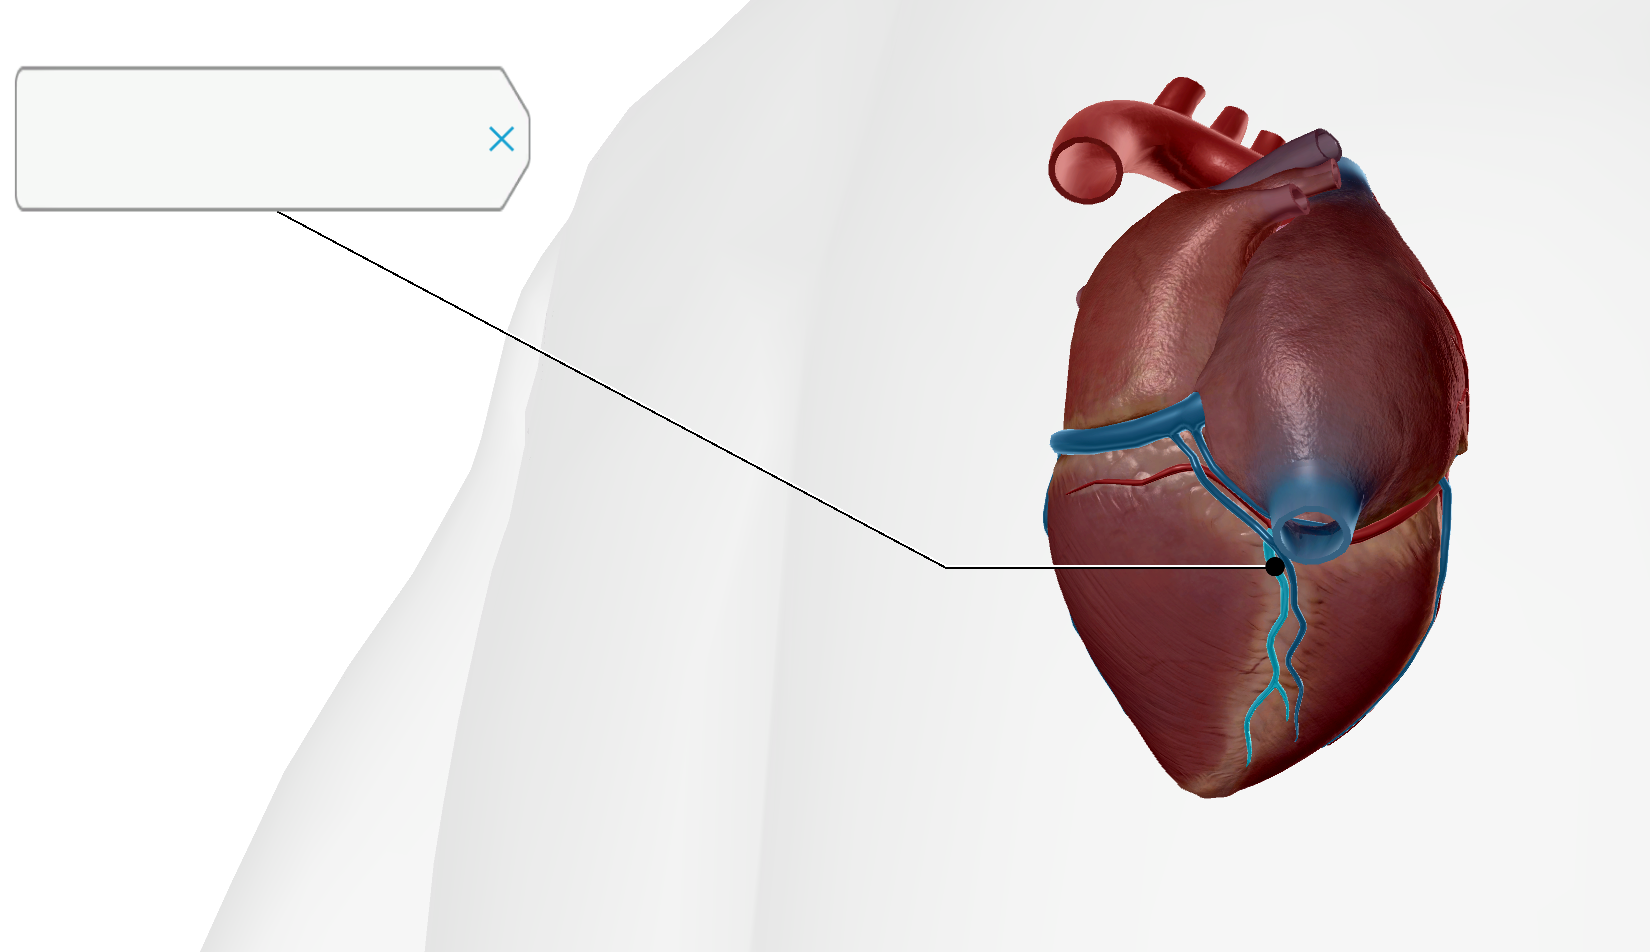

AV Node

SA Node

Bundle of His

Coronary Sinus

Coronary Sulcus

Posterior Interventricular Sulcus/Artery